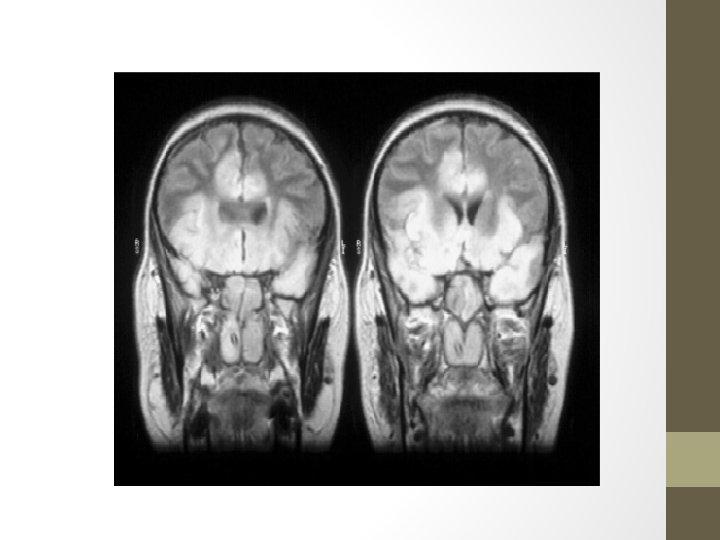

Herpes simplex encephalitis The majority of cases of herpes simplex encephalitis (HSE) in adults are caused by HSV-1. 10% are caused by HSV-2, usually associated with immuno-compromise or occurring in the neonate. The herpes virus leads to inflammation, infection and necrotizing lesions particularly in the inferior and mesial temporal lobes which may also involve the orbital frontal cortex and limbic structures.

• Diagnosis q. The EEG show periodic sharp-wave complexes from temporal lobe on low amplitude background q. CT-scan low density lesion within the temporal lobe with mass effect. q. MRI-high signal intensity on T 2 q CSF-Lymphocytic pleocytosis, elevated protein, normal or glucose q. PCR to detect HSV DNA in CSF q. CSF may contain RBCs (due to necrosis in the brain tissue)